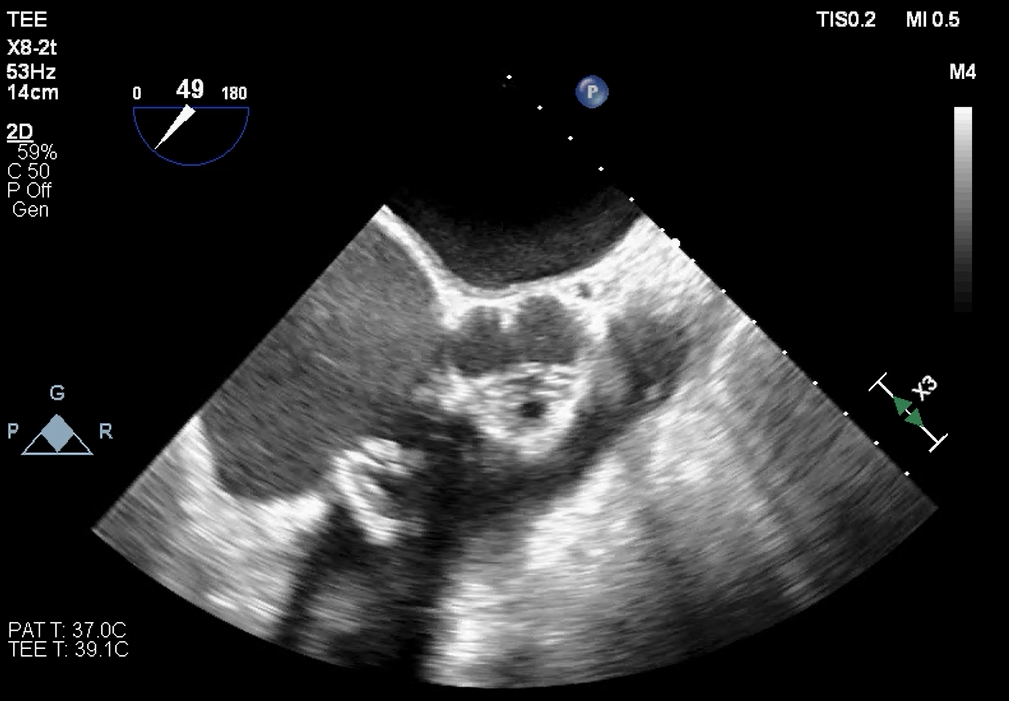

超声提示

影像分析

生物瓣金属内径28.9mm

面积折算直径21.6mm

周长折算直径21.8mm